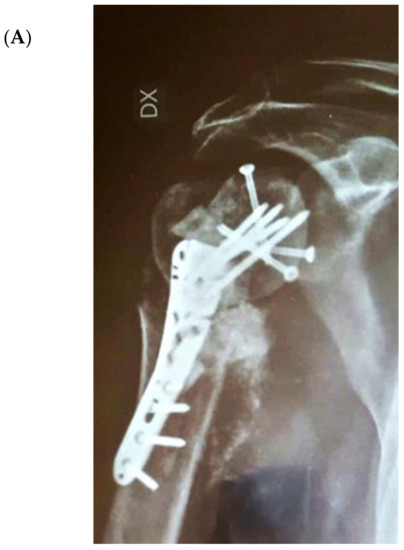

The bone substitute GlassBONE Putty (Noraker, Villeurbanne, France), made of bioactive glass, was routinely employed in revision surgeries requiring bone loss filling in our surgeries. This ceramic is composed of Silicium, Calcium, Sodium and Phosphorous, minerals which are naturally present in the human body; it is in a ready-to-use format and can be injected through the syringe (Figure 1): it may be used both to increase prosthesis-bone interface stability and fill bone defects in PJIS revision surgeries, also contributing to preventing re-infection. In this regard, a peculiar case was reported (Figure 2): infection after percutaneous treatment of a proximal humerus fracture. The pinning removal and the implant of a cement antibiotic spacer were attempted. Finally, an RSA (Equinoxe Shoulder System, Exactech Inc., Bloomington, MN, USA) was implanted with the addiction of bioactive glass to prevent tuberosity defect augmentation and re-infection.

Figure 2.

An infection after percutaneous pinning of a proximal humerus fracture. (A) Preoperative X-ray. (B) The subsequent implanting of a cement antibiotic spacer (red circle underlines bone loss); (C) the final reverse arthroplasty (RSA) with the addition of bioactive glass in the tuberosity defect.